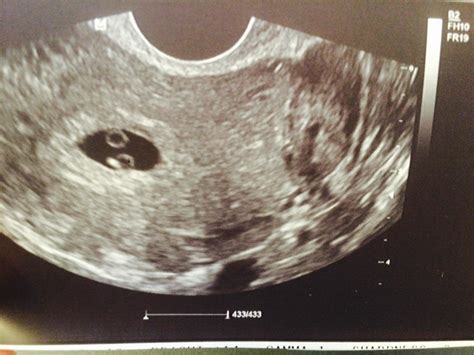

It is natural to wonder exactly what will be visible. At the first ultrasound pregnancy, the images might look a bit abstract if you aren't familiar with reading them. The sonographer will guide you through what is on the screen, but here is what you might expect to see:

The Gestational Sac: Early on, the first sign of pregnancy is the sac that holds the embryo.

The Yolk Sac: This small, circular structure provides nourishment to the developing embryo before the placenta takes over.

The Fetal Pole: This is the embryo itself. At 6 or 7 weeks, it looks very small, but you may be able to see the rhythmic flickering of the heartbeat.